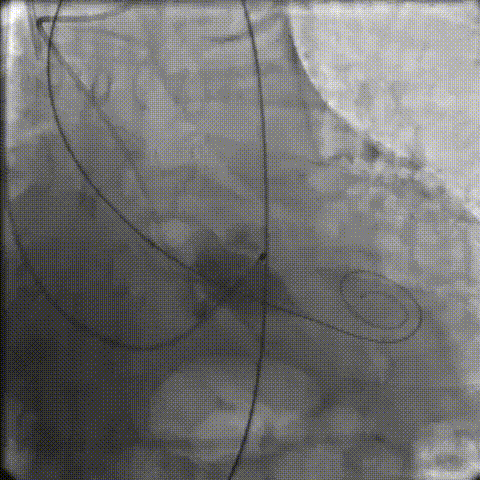

手术影像记录

主动脉根部造影

18mm球囊预扩

零位定位逐步释放至工作位,多角度评估位置良好

缓慢脱钩至完全释放,最终植入位置理想